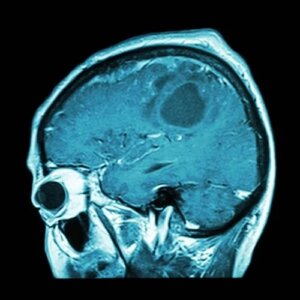

Vaccinurile sunt modalități excelente de prevenire și vindecare a bolilor. Astfel, este de înțeles de ce cercetătorii caută diferite modalități de a pune capăt cancerelor agresive, precum cancerul cerebral. Există deja vaccinul contra cancerului cerebral?

Imunoterapia este un concept extrem de relevant în cazul acestui vaccin pe care experții l-au descoperit recent. Acest termen se referă la utilizarea propriilor mijloace de apărare ale organismului pentru a direcționa și a ataca cancerul cerebral.

Cu toate acestea, cercetătorii au descoperit că nu toate tumorile sunt la fel și nici nu răspund la fel de bine la tratamentul prin imunoterapie. Din acest motiv, s-a lucrat la „imunoterapia de precizie” pentru a trata pacienții care suferă de glioblastom.

Glioblastomul este unul dintre cancerele cu cel mai slab prognostic. Prin urmare, pacienții au nevoie de un vaccin personalizat pentru a exista rezultate favorabile. Dar cum fac acest lucru experții?